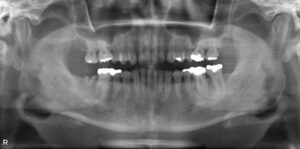

下顎大臼歯1本欠損症例

BEFORE AFTER 34歳女性/下1本欠損/インプラント埋込手術 【治療内容】 右下第二大臼歯のインプラント治療を…